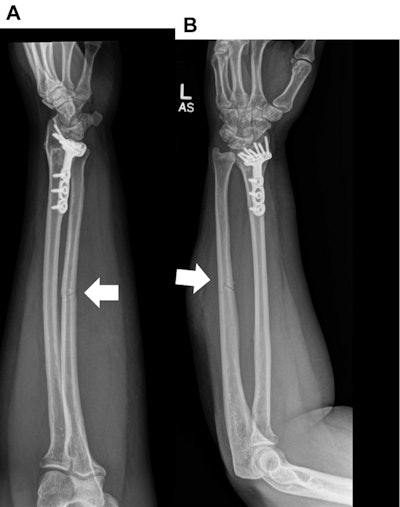

A 34-year-old woman with a history of motor vehicle collision. (A) Lateral and (B) frontal radiographs of the left forearm show a comminuted mildly displaced fracture of the mid-diaphysis of the left ulna (wide bold arrows).Confirmed cases of intimate partner violence in the study were also associated with homelessness, with 45.5% of women in the confirmed category being reported as homeless (p < 0.01).